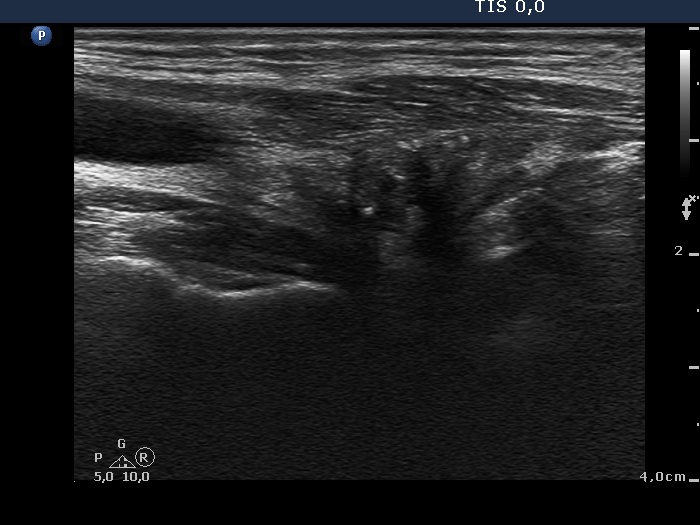

Four months after surgery (ultrasonographic picture 2)

Right lobe, longitudinal scan

Right lobe, longitudinal scan. The extent of the regenerative tissue has decreased.